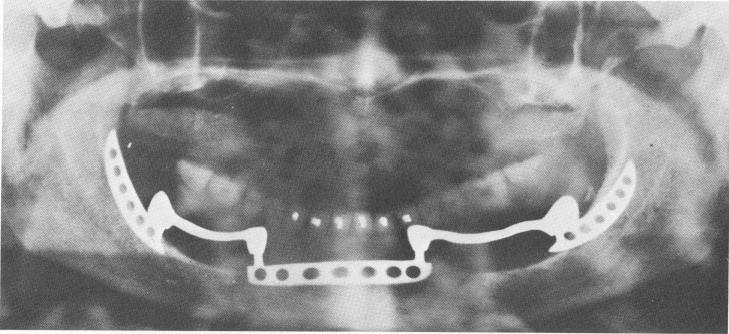

cording to Dr. Harold Roberts, there still remains serviceable bone in the retromolar area and in the ramus. Thus Roberts developed the retromolar blade implant (Fig. 11-147) .

The retromolar blade implant is placed into the bone by first making a long incision along the fibromucosal tissue covering the alveolar crest. The mesial limit of the incision is approximately 28 mm. distal to the mental foramen and extends distally approximately 18 mm. A groove is cut with a No. 560 bur immediately below the incision into the cortical bone, extending distally approximately 14 to 18 mm. to the entire depth of the bur (5.5 mm.) . The distal end of the sickle-shaped implant is then inserted into the slot in the bone below the cortical plate and is tapped distally into the medullary portion of the ramus between the buccal and lingual cortical plates until the mesial lip of the blade portion of the implant clears the anterior margin of the bony slot. Since the inferior surface of the implant is rounded, it slips gently into place posteriorly into the ascending ramus. A grooved chisel and plastic-headed mallet are all that is necessary for this procedure. With a crown and bridge remover locked be-hind the distal proximal surface of the protruding post, the implant is gently tapped menially so that the mesial spur of the implant locks under the cortical plate that forms the anterior limit of the bony slot. The flaps of the soft tissue are repositioned and sutured around the protruding post. The sutures are removed in 5 to 7 days.

Fig. 11-147. Retromolar blade implant abutments in combination with an anterior blade acting as abutments for a removable prosthesis. (Courtesy Dr. Harold Roberts.)

1 Retromolar blade implant abutments & anterior blade in mandibular arch